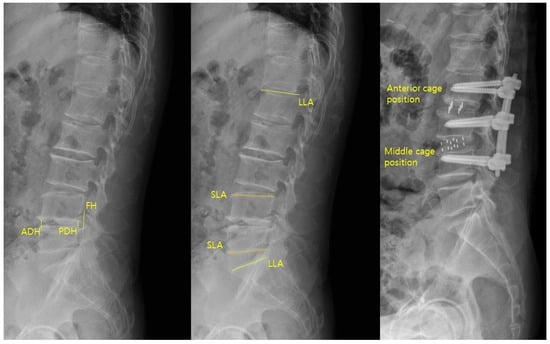

HU values were measured on axial CT images at three levels (upper, middle, and lower thirds) of both the superior and inferior vertebrae body adjacent to the surgical disc space (Figure 1). Regions of interest (ROIs) were placed centrally in the trabecular bone, avoiding cortical margins and venous channels. The centre of each ROI was targeted to the central portion of the vertebral body, and the ROI area was set to include more than 50% of the vertebral body cross-sectional area while avoiding inclusion of the cortical bone.

Metal artefacts from posterior instrumentation were carefully avoided during ROI placement. All CT images were acquired with a slice thickness of 1–3 mm. The mean of three measurements for each vertebra was calculated, and the final HU value per surgical level was the average of the superior and inferior values [17]. CT scans were obtained using a multidetector CT scanner (Ingenuity, Philips Healthcare, Eindhoven, The Netherlands).

Sagittal parameters were assessed using preoperative and postoperative lateral lumbar radiographs (Figure 3). The parameters were anterior disc height (ADH), posterior disc height (PDH), foraminal height (FH), segmental lordotic angle (SLA), and lumbar lordotic angle (LLA). ADH and PDH were defined as the vertical distances between the superior and inferior endplates at the anterior and posterior margins of the surgical level, respectively. FH was the maximum vertical distance between the inferior pedicle of the upper vertebra and the superior pedicle of the lower vertebra. SLA was the Cobb angle between the superior endplate of the upper vertebra and the inferior endplate of the lower vertebra at the surgical level. LLA was the Cobb angle from the superior endplate of L1 to the superior endplate of S1. Postoperative cage position was categorized as anterior one-third (anterior group) or middle one-third (middle group) of the inferior endplate [3]. All measurements were performed using PACS workstation software (INFINITT G3, INFINITT Health care, Seoul, Republic of Korea).

Figure 1. Hounsfield units were measured on axial CT images by averaging the values from three ROIs within the trabecular bone of both adjacent vertebrae at the surgical level.

Figure 3. Sagittal parameters of ADH, PDH, FH, SLA, and LLA were measured on lateral radiographs, and cage position was categorized as anterior or middle based on its location on the inferior endplate.